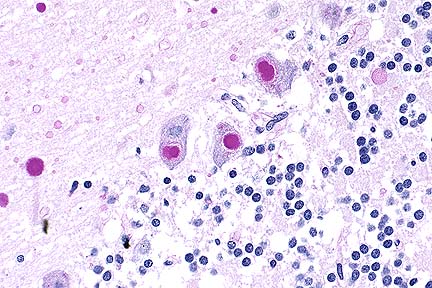

Higher magnification of the field above, showing cytoplasmic inclusions within several Purkinje cells, as well as inclusions in unidentified cells in the molecular layer. (HE, 400X, 48K)

In sections of brain, there are few to many basophilic to amphophilic inclusions that occur within the cytoplasm of nerve cell bodies, neuronal processes, and scattered in the neuropil. These inclusions are usually round, range in size from 2 to 10 um diameter, and occasionally have a pale center or a thin, striated halo. These Lafora-like bodies are most numerous in the cerebellar molecular layers and within Purkinje cells, but are observed in all examined sections of brain.

Lafora bodies consist of complex polymers of glycoprotein, sometimes designated "polyglucosan bodies", and can occur within neuronal cell bodies or processes of the brain, spinal cord, or retinal ganglia. The round to globular basophilic cytoplasmic inclusions stain positively with PAS, alcian blue, and methenamine silver. In domestic animals, Lafora bodies have been observed most commonly in aging (at least 8 years of age) dogs and cats without apparent neurologic disease, but have also been described as incidental changes in some young animals. Lafora bodies have also been associated with a severe form of progressive myoclonus epilepsy in humans (juveniles) and dogs (young adult to middle-age), reflecting widespread intra-neuronal storage of these polyglucosans ("Lafora disease" or "neuronal glycoproteinosis"). The absence of other lesions to account for the observed neurologic signs incriminates the Lafora bodies as playing a role in the reported neurologic signs in this cat. In dogs with associated neurologic disease, the deposits are most commonly observed in Purkinje cells, similar to the distribution noted in this cat. In children with Lafora disease, other sites of polyglucosan deposition include skin and liver, and biopsies of these tissues have been used to help establish the diagnosis. Lafora bodies were not found in tissues from other than the CNS in this cat.

Conference Note: This case was also reviewed by AFIP's Department of Neuropathology. Lafora bodies are complex glycoprotein neuronal inclusions that can occur in the perikaryon, dendrites, or axons. They are PAS-positive and stain with alcian blue and methenamine silver. They can be found anywhere in the neuraxis and in retinal ganglion cells. Polyglucosan bodies have been associated with neurologic disease in humans, cats, dogs (Beagles, Basset Hounds, and Poodles), and a cockatiel. Lafora's disease in humans is a rare familial neurologic disorder of children. The disease is progressive and manifested by myoclonus. The characteristic histologic feature in the human disease is intraneuronal polyglucosan bodies, which occur predominantly in the substantia nigra and dentate nucleus. In dogs with neurologic disease attributed to the accumulation of intraneuronal polyglucosan bodies, the bodies are found predominantly within Purkinje cells and in thalamic neurons. In animals, Lafora bodies are frequently seen in the absence of neurologic disease. In these cases, the Lafora bodies can be found in any area of the brain and in the spinal cord.

Ultrastructurally, Lafora bodies have electron-dense fibrillary and sometimes granular components. They are not membrane bound and are often associated with rough endoplasmic reticulum and golgi apparatus.